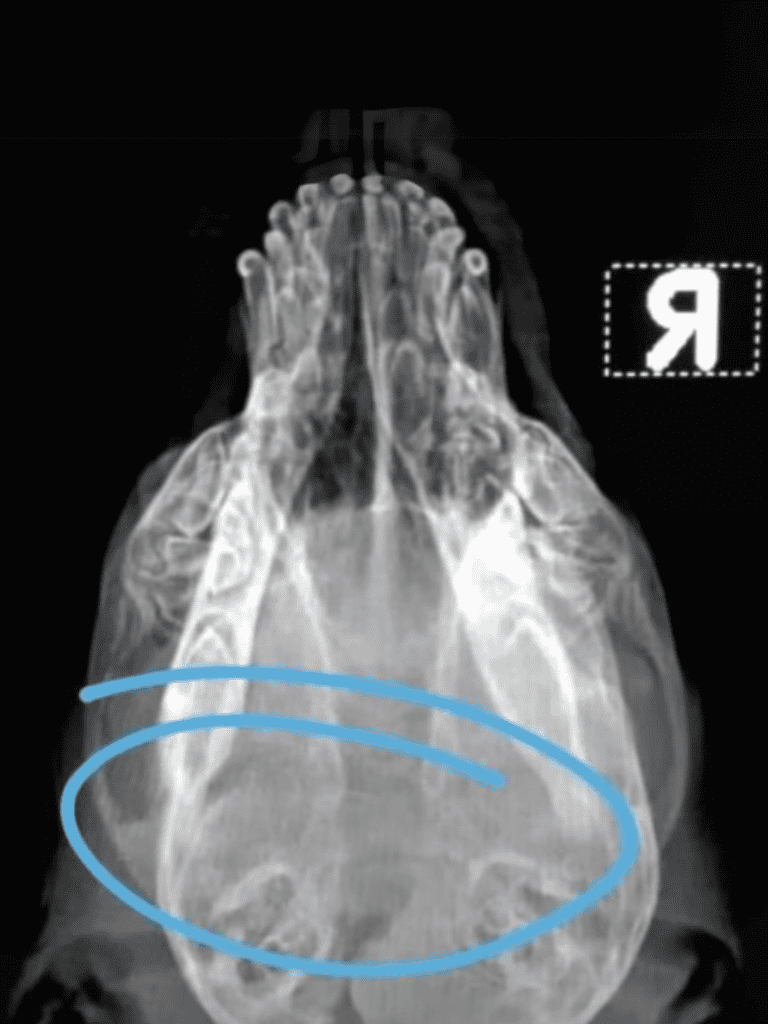

Ollie’s fractured skull was a reminder of the cruelty he endured. Doctors could only manage the pain and swelling.

Brain Swelling

The swelling on Ollie’s brain was the doctors’ primary concern. They monitored closely, hoping for improvement.

If it subsided, they could assess the damage. Until then, they could only wait and hope.

Ollie underwent a procedure to drain fluid from his head. Despite challenges, he shows resilience and takes a step toward healing.